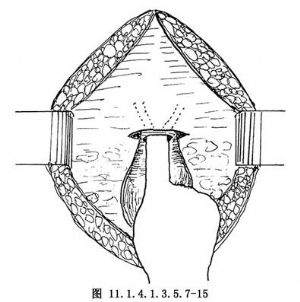

11.6 6.剪開闊韌帶後葉

於子宮骶骨韌帶水平剪開闊韌帶後時,下推直腸達宮外口(圖11.1.4.1.3.5.7-15)。